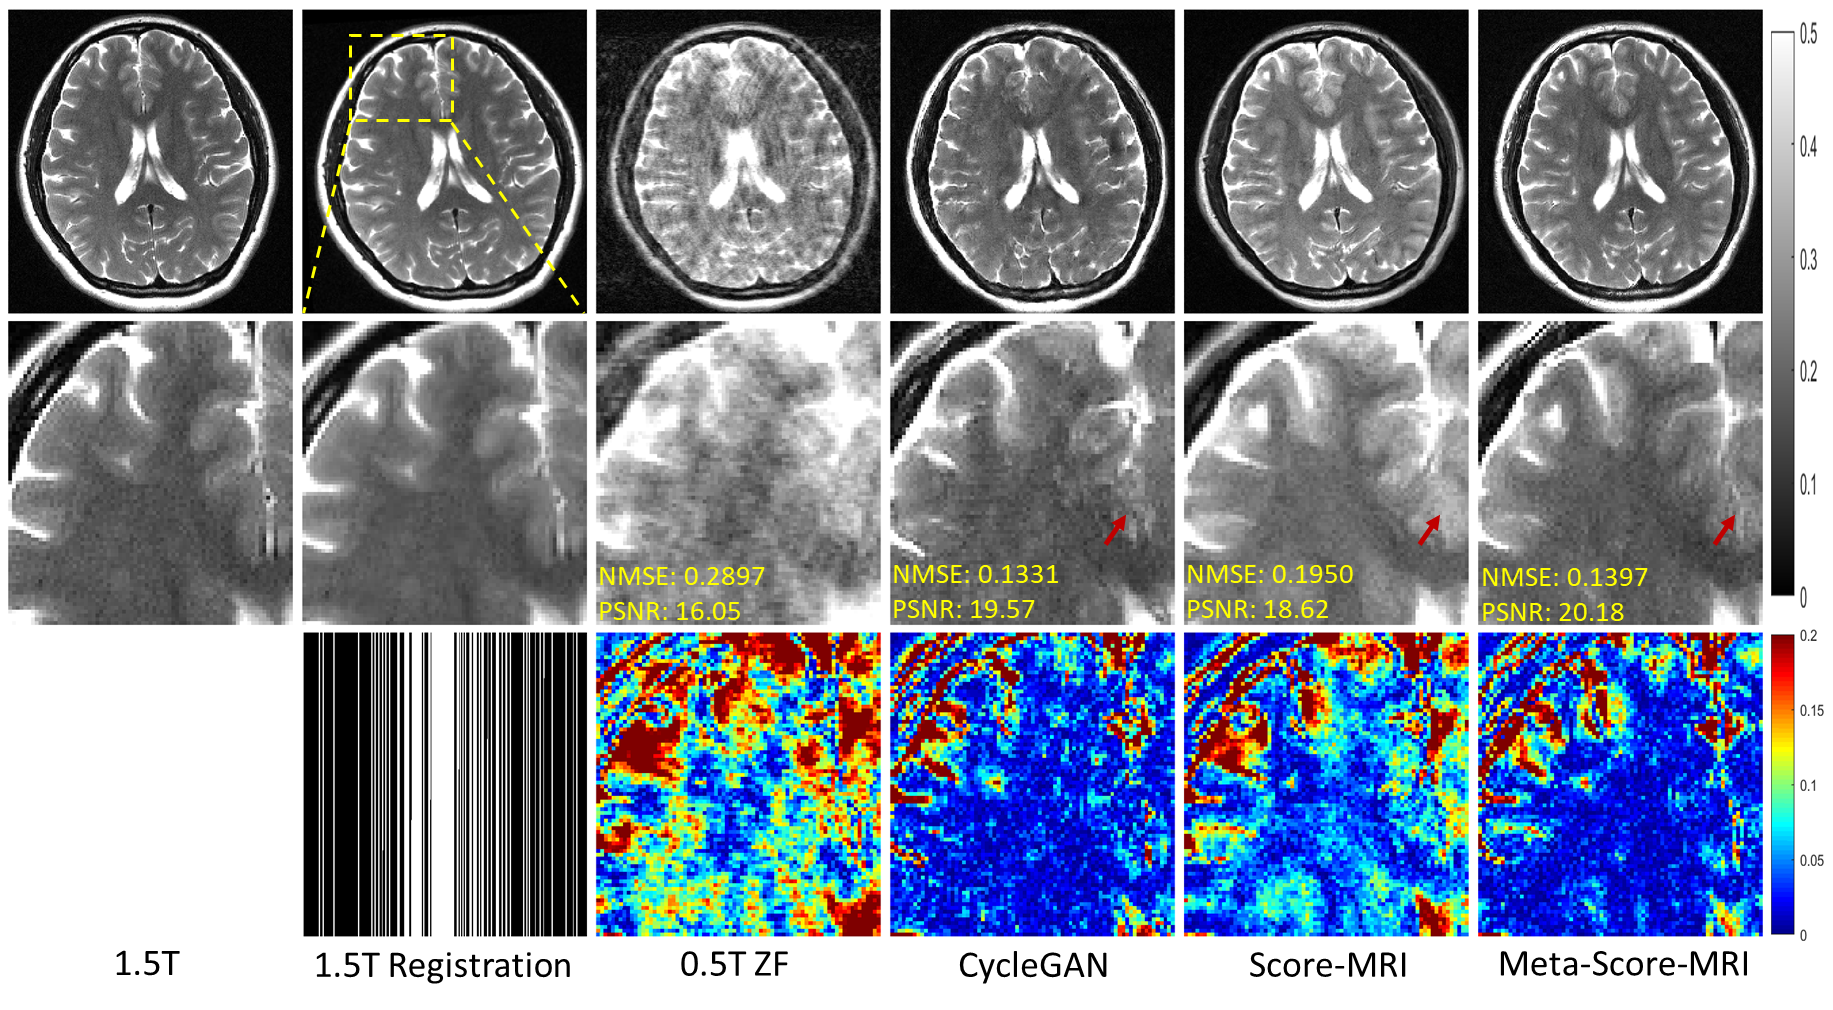

This section presents the testing of various methods on full-sampled 0.5T MRI data, with the aim of reconstructing 1.5T-like MR images and eliminating the ill-posedness outlined in (2). The results of the different methods used in reconstructing 1.5T-like T2W images are shown in Figure 3. The images obtained from the 0.5T MRI are observed to have reduced SNR and contrast degradation when compared to the 1.5T images.

Among the reconstruction methods employed, it was discovered that CycleGAN yielded results with similar contrast to actual 1.5T images. However, magnified images revealed visible artifacts, thus validating Theorem 3.1, which postulated that there is no OT mapping from 0.5T to 1.5T images. On the other hand, the Score-MRI method only considered SNR degradation in 𝒇𝒇\bm{f}, as captured in model (6), while ignoring contrast degradation. As a result, its experimental outcomes were in line with its modeling, with improved image SNR, but no change in contrast relative to the 0.5T images.

The proposed method, Meta-Score-MRI, reconstructed 1.5T-like images that were visually almost indistinguishable from the real 1.5T images in terms of SNR and contrast. Notably, Score-MRI’s modeling was inaccurate, leading to blurry image details, as indicated by the red arrow. In contrast, the proposed method accurately reconstructed these details, further validating the superiority of the proposed method’s modeling captured in equation (7).

Refer to caption

Figure 3: Reconstruction of 1.5T-like T2W MR Images from full-sampled 0.5T T2W MRI. The first line showcases the original 1.5T MR image, while the second line demonstrates the registration of the 1.5T image with the shape of the 0.5T MR image. The third line showcases the 0.5T MR image. The resulting reconstructed images are depicted in lines four through six. On the other hand, the second row offers an enlarged view, and the third row shows the error view between the generated 1.5T-like image and the registered 1.5T image. The NMSE/PSNR values of the enlarged view are displayed in the corners. The grayscale of the reconstructed images is visible on the right side of the figure.